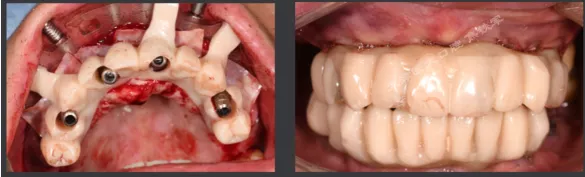

下颌即刻种植即刻修复手术过程

· 下颌士卓曼360数字化序列导板+预成临时修复体

· 翻瓣,利用松牙固定后的余留牙支持连接在一起的牙支持导板和基部导板,使骨支持的基部导板就位于骨面。

· 并用固位钉固定,拆除牙支持式导板,拔除余留牙。

· 基部导板上缘做为截骨线,精确去骨,平整骨面。

· 全程植入导板就位于基部导板上,固位钉固定,引导种植体植入。

· 种植体植入后,安装复合基台基底

· 临时修复体就位于基部导板,固位钉固定,口内Pick-up后取下修改,戴回口内,咬合关系良好。

上颌即刻种植即刻修复手术过程

· 上颌360数字化序列导板+预成临时修复体

· 拔除部分牙齿,翻瓣,利用剩余牙齿支持组合导板,辅助基部导板就位固定,基部导板上缘做为去骨线,精确去骨。

· 全程导板就位,引导种植体植入,安装复合基台。

· 种植体植入位置偏腭侧,唇侧骨量过于丰满,上颌骨前突,去骨修整骨边缘。

· 口内pick-up 固定临时修复体,患者上下颌咬合关系良好。